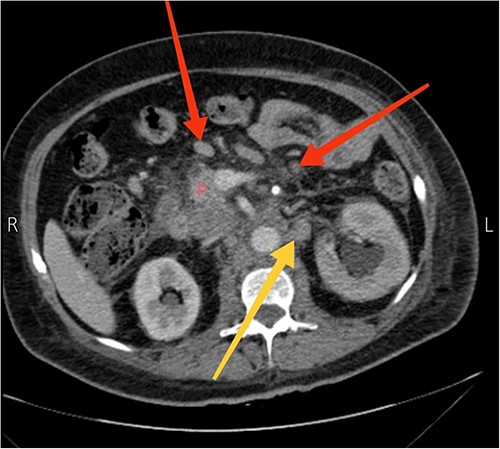

A 57-year-old female presented to our emergency department with diffuse abdominal pain, distention, constipation, nausea, and back pain of one-month duration, accompanied by a 19.8 lbs (9 kg) weight loss. Three months earlier, the patient sought care at another hospital for recurrent abdominal pain. Computed tomography (CT) scans revealed suspiciously enlarged lymph nodes in the peripancreatic and para-aortic regions, notably a 4.1 × 2.4 cm necrotic and heterogeneous node in the para-aortic area (Fig. 1). Subsequent ultrasound-guided fine needle aspiration and fine needle biopsy confirmed a metastatic poorly differentiated adenocarcinoma and an acellular smear, respectively. Upper and lower endoscopic studies showed unremarkable findings. The diagnosis of CUP origin was made.

Axial view CT scan showing the head of the pancreas (P), enlarged peripancreatic lymph nodes (the two arrows at the top), and a 4.1 × 2.4 cm necrotic and heterogeneous enlarged lymph node in the para-aortic area (the arrow at the bottom).